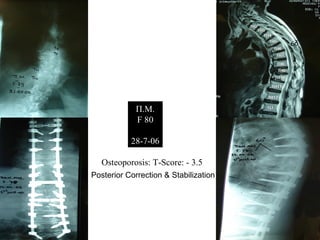

Π.Μ.

F 80

28-7-06

Osteoporosis: T-Score: - 3.5

Posterior Correction & Stabilization